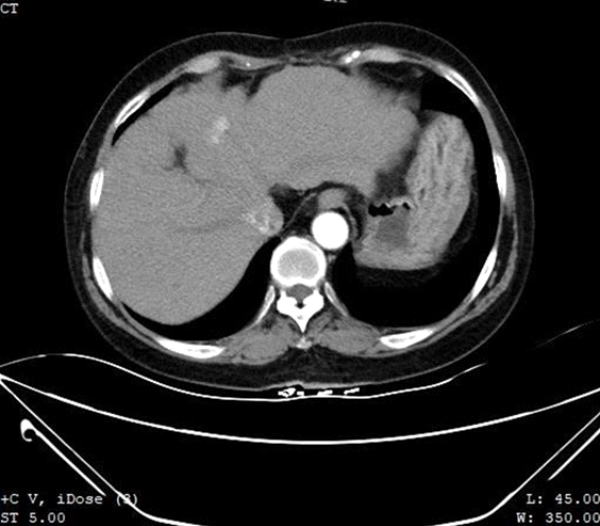

64? ???? 30? ??? ??B? ?? ??????, ???? S7?? ???? ??? ???? ?????? ?????. 3?? ?? MR? S4 ??? ?? ??? ?? ???? ???? ??? ??????. ???? Contrast-enhanced CT(??? ?? CT??)? ???? ?? S4 ??? 1.5???? ?? ???? ???? ??? ???????. ??? ??? ??? ???? ??? ??? ??? ??? ?????.

CT??? ??? S4?? ??? ??? ?? ???????? ??? ?????. CEUS(Contrast-Enhanced Ultra Sound)????? ?????? ??? ??? ??? ??? ???? ? ??? ???? ???? ??? ???????.

??? ??? ?? ????? ???(MWA)? ?? ?????? ?? ?????? ??? ???? ??? ?? Contrast-enhanced CT? ???? ??? ?? ??? ??? ?? ??? ?? ??? ????? ???? ???? ????? ??(MWA)? ??? ???????.

??? ????? ??? 2D ??? ??? ???? ???? ???? ??? ? ????? ??? ??? ?? ?????? ???? ?? ??? ???? ???? ??? ? ?????. ??? ??? ???? ??? ?? CT ??? ??? ???? ??? ??? ??? ?? MWA? ?? ???? ??? ???? ?????. CEUS(Contrast-Enhanced Ultra Sound)? ???? ?? ? ??? ??? ????, ?? ? ?? ??? ???? ?? ?? ??? ???????.?